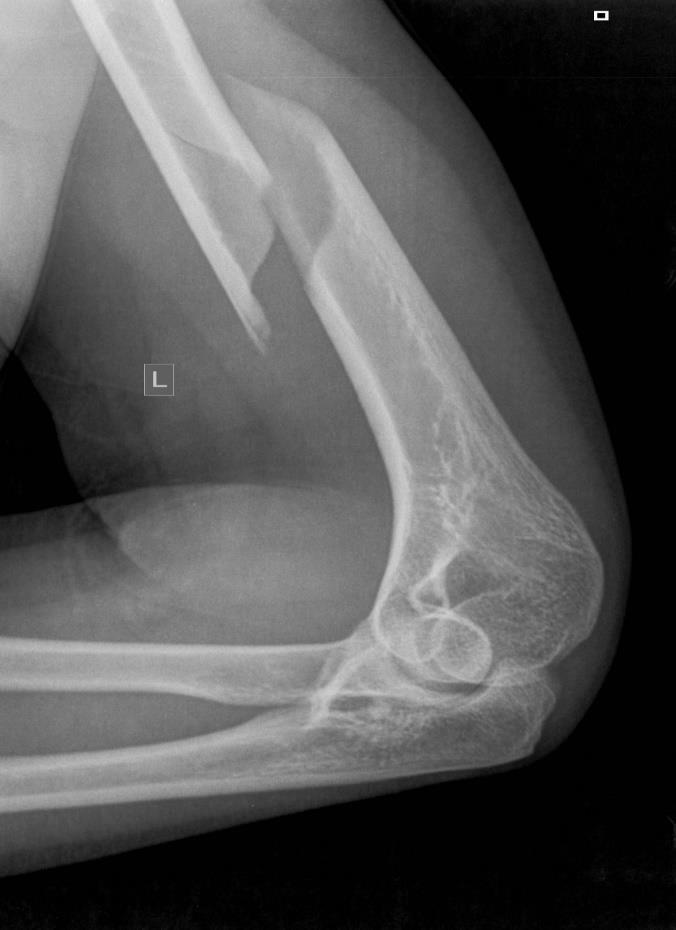

Wskaż jakim symbolem należy oznaczyć według klasyfikacji AO i jak powinno być leczone złamanie widoczne na zdjęciu:

Złamanie poprzeczne gałęzi kości łonowej współistniejące ze złamaniem talerza kości biodrowej typu półksiężyca (crescent) odpowiada wg klasyfikacji Younga i Burgessa typowi: